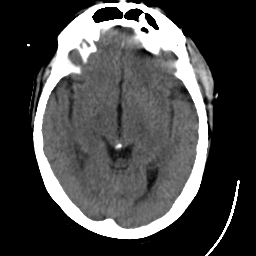

Meningioma: Roentgen-ray CT #1 -- Slice #9

[Home][Help][Clinical] Slice 9